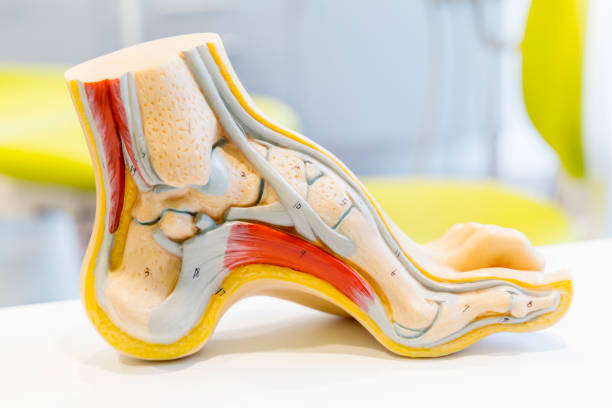

발뒤꿈치가 아픈 이유 첫 번째는 족저근막염입니다. 족저근막은 발뒤꿈치 뼈에서 시작하여 발바닥 앞쪽으로 연결되는 두껍고 강한 섬유질 띠입니다. 족저근막은 우리 몸의 중요한 역할을 하는데 아치 모양의 모양새는 우리 몸의 체중을 흡수하기 때문에 걷는 데 중요한 역할을 할 수 있습니다. 족저근막염은 이러한 족저근막에 반복되는 충격으로 근막을 둘러싸고 있는 콜라겐이 변성하면서 염증이 생긴 것을 의미합니다.

발뒤꿈치가 아픈 이유 3. 점액낭염

발뒤꿈치가 아픈 이유 세 번째는 점액낭염입니다. 점액낭은 아킬레스건의 움직임을 부드럽게 해주는데 이 역시 반복된 충격을 가하기 때문에 발뒤꿈치에 통증이 생길 수 있습니다. 다만 아킬레스건과 다르게 평소에도 통증이 지속되기 때문에 지속적인 관리를 해야합니다.